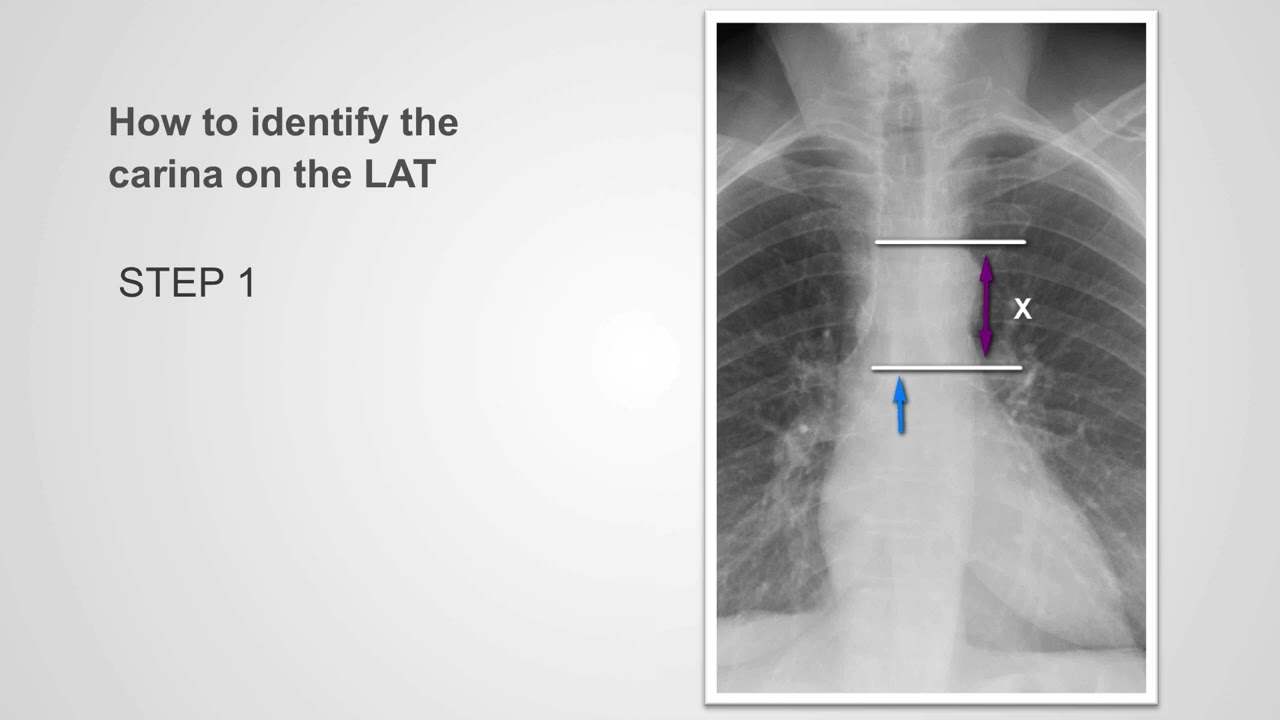

04. How to confidently identify the carina - YouTube